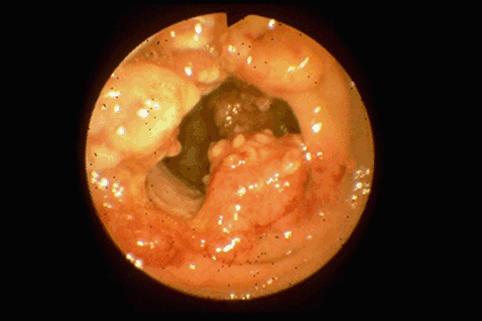

Sindrome de Prolapso de Mucosa Rectal que mostró formación semejante a tumor maligno

Enfermedad Inflamatoria - Ulcerativa/Sindrome de Prolapso de mucosa rectal

colon/recto

Endoscopia

35 - 40